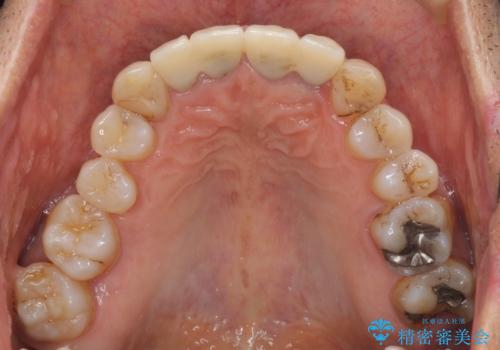

- 昨年治療した前歯の根尖部に痛みを感じ、ラバーダムや顕微鏡を用いた根管治療を希望されて、転院された患者様です。

前医にて神経を取り除いた処置を行った際、ラバーダムが使用されなかったとのことで転院されてきました。

根管治療を実施した後、オールセラミッククラウンに補綴することとしました。